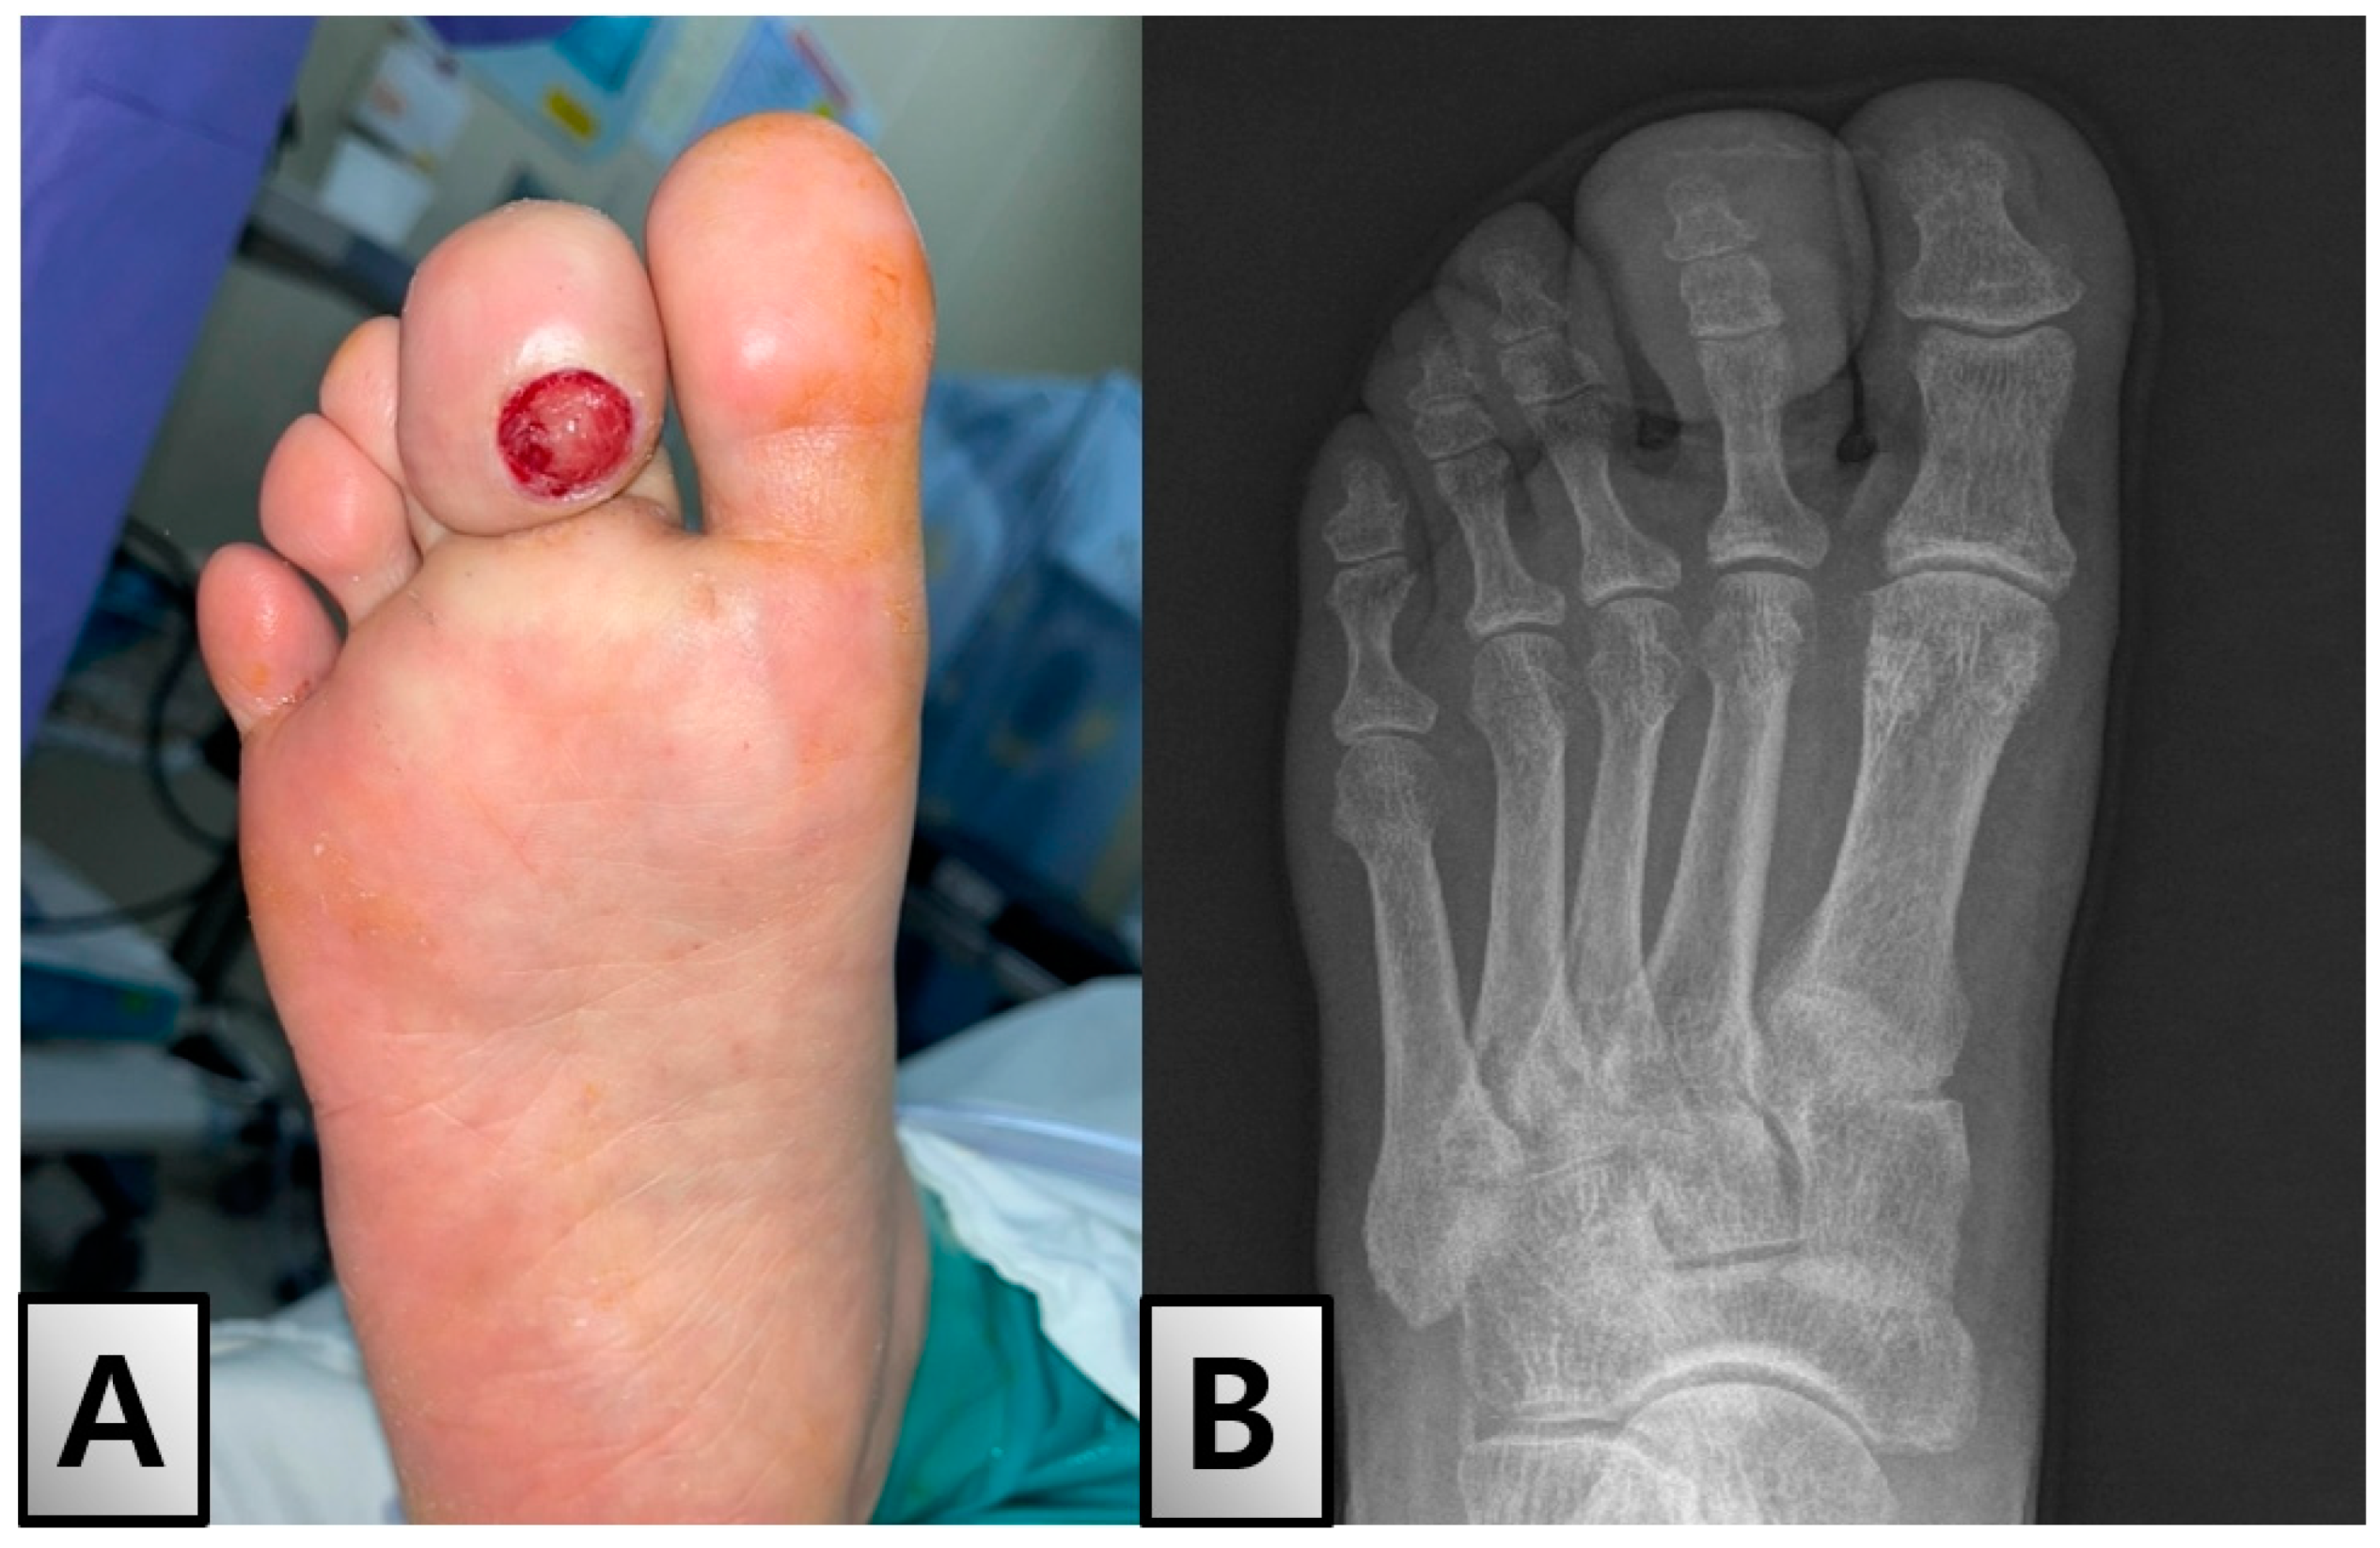

A Rare Case of Solitary Neurofibroma Misdiagnosed as Diabetic Foot Ulcer in the Toe Tip Region

2. Case Presentation